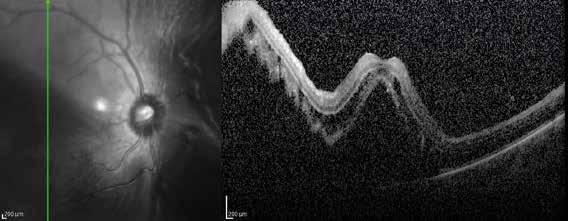

Figure 2. Multimodal imaging of right eye of a male diabetic patient affected by PDR and DME. 2A-B) UWF pseudocolor retinography (Optos Silverstone, Optos, UK) and corresponding magnification of macular region showing diffuse hard exudates and intraretinal hemorrages; 2C) OCT (Heidelberg Spectralis, Heidelberg Engineering Inc., Germany) displaying diffuse center-involving DME; 2D-E) Late phase UWF FA (Optos Silverstone, Optos, UK) and corresponding magnification of macular region presenting extense breakdown of BRB with perivascular leakage and non-perfusion areas, pooling effect compatible with MA and masking effect due to pre-retinal hemorrhages. Two leakage spots associated to possible NVs close to inferior vascular arcade; 2F) 3x3 B-scan OCT-A (Zeiss PLEX Elite 9000, Carl Zeiss, Germany) showing flow signal within pre-retinal NV.

Figure 3. Multimodal imaging of a male diabetic patient affected by PDR and DME that has already been treated by incomplete laser photocoagulation therapy. 3A) UWF pseudocolor retinography displaying hard exudates and intraretinal hemorrhages within vascular arcades and peripheral laser photocoagulation therapy; 3B) UWF SS-OCT showing focal center-involving DME; 3C) Late phase UWF FA (describing mild BRB disruption with 2 leakage areas compatible with NV along inferior vascular arcade; 3D) 15x15 En-face WF-SS-OCTA presenting FAZ enlargement, diffuse capillary drop-out and temporal mid-peripheral retinal nonperfusion areas, and two pathological vascular networks associated to NVs.

Figure 4. Multimodal imaging of a female diabetic patient affected by PDR that has already undergone complete laser photocoagulation treatment. 4A) UWF pseudocolor retinography showing complete laser photocoagulation treatment until vascular arcades; 4B-C) 12x12 and 4E-F) en-face WF-SS-OCTA of diabetic patient (4B, 4E) presenting FAZ enlargement, diffuse capillary drop-out and inferior mid-peripheral retinal nonperfusion areas, as compared to healthy patient (4C, 4F; 4D) Late phase UWF FA displaying diffuse BRB breakdwon, with perivascular leakage and non-perfusion areas.

5. Multimodal imaging of a

diabetic patient affected by

5A) UWF pseudocolor retinography showing some hard exudates within and outside vascular arcades; 5B) Late phase UWF FA presenting far peripheral BRB rupture, with associated perivascular leakage and retinal ischemia, and diffuse pooling effect within telengectasic vessels; 5C) UWF SS-OCT, displaying some hard exudates close to optic disc.

OCT-A) (Figures 2-5).